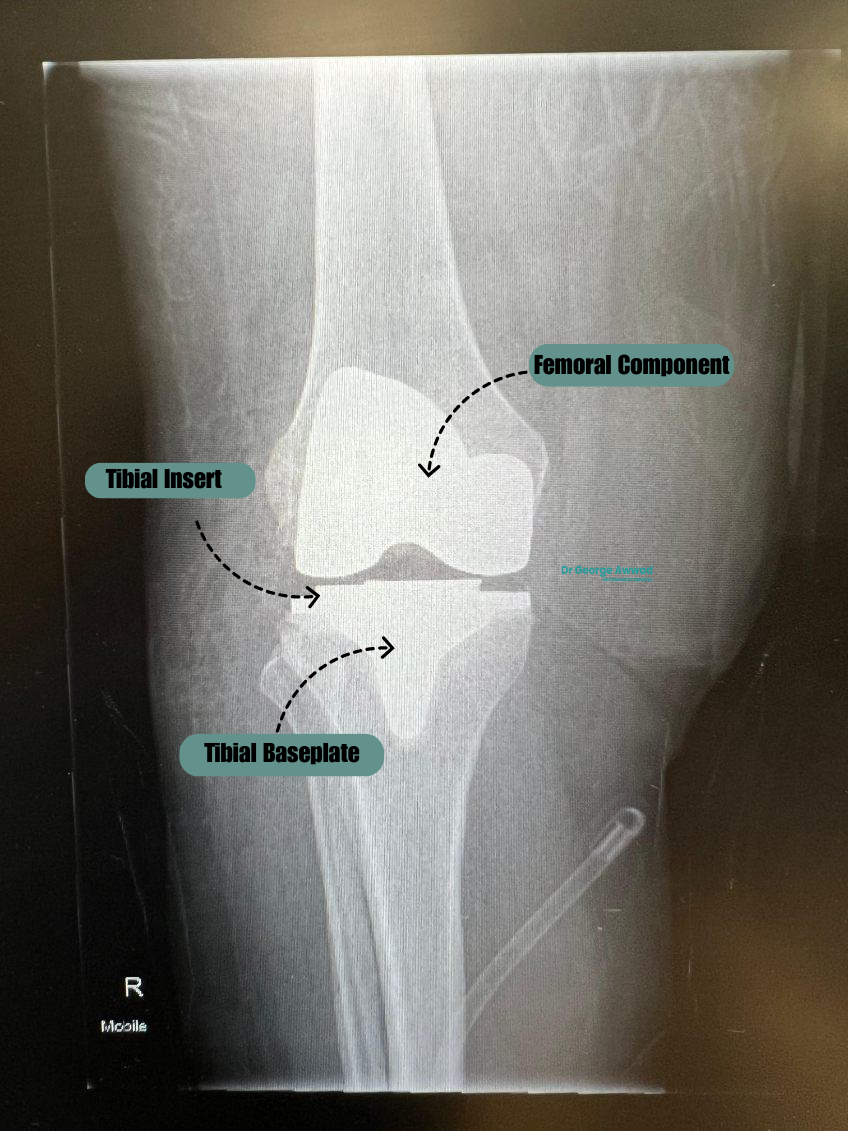

Total knee replacement (TKR)

In a total knee replacement, the worn-out surfaces of the knee joint are replaced with prosthetic components:

- Medial compartment (inside of the knee)

- Lateral compartment (outside of the knee)

- Patellofemoral compartment (under the kneecap) also often replaced but only when required

The procedure involves carefully removing damaged cartilage and bone and replacing them with metal and plastic implants that restore joint function. This is the most common form of knee replacement and is typically recommended when arthritis or degeneration affects the entire joint.

Main components of a knee replacement implant

- Femoral component – This metal piece caps the end of the thigh bone (femur) and may be curved to match the natural shape of the femur. It allows smooth movement against the tibial component.

- Tibial component – Placed on top of the shin bone (tibia), this component consists of a metal baseplate and a polyethylene (medical-grade plastic) insert that acts as a cushion and bearing surface.

- Patellar component – In some cases, the underside of the kneecap (patella) is also resurfaced with a polyethylene dome to improve joint tracking and movement.